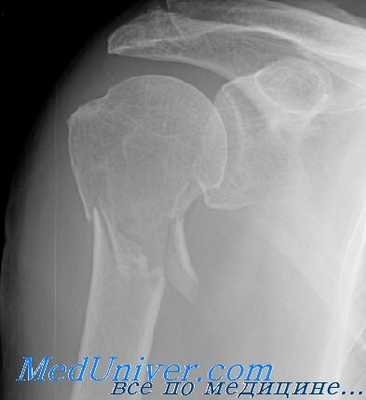

Серия рентгенограмм при повреждениях, рекомендованная Neer, очень помогает оценке переломов проксимального отдела плечевой кости. Кроме того, авторы рекомендуют снимки в переднезадней проекции с внутренней ротацией конечности и в аксиллярной проекции. Эти четыре проекции позволяют провести полную оценку плечевого сустава и проксимального отдела плечевой кости, включая суставную поверхность. Эти снимки можно делать больному в положении лежа, стоя или сидя, хотя авторы рекомендуют положение сидя.

Для уточнения диагноза назначают рентгенографию плечевого сустава в двух проекциях: прямой и «эполетной» (аксиальной). «Эполетный» снимок выполняют, отводя плечо от туловища под углом 30-40 градусов. Большее отведение категорически не рекомендуется, поскольку может усугубить смещение отломков. В сомнительных случаях используют КТ плечевого сустава. При подозрении на сдавление сосудисто-нервного пучка пациентов направляют на консультацию к неврологам или нейрохирургам и сосудистым хирургам.